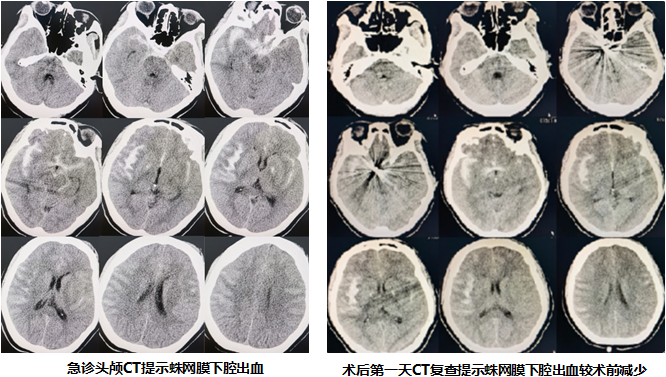

41王大姐(化名)于沐浴中突发头痛,剧烈难忍,约10分钟后意识不清。急诊来石岩人民医院行头颅CT检查提示蛛网膜下腔出血,大脑被广泛的血性液体浸泡,引起严重脑水肿和脑血管痉挛(血管强制收缩后导致管腔变细,所供应的脑组织缺血),是导致头痛和昏迷的直接原因,甚至导致死亡。

CTA(头颈部血管检查)明确右侧后交通动脉瘤,是这次致命性出血的罪魁祸首。手术团队制定详细手术方案,决定急诊行右侧远端桡动脉入路动脉瘤栓塞术。

经远端桡动脉入路行动脉瘤栓塞,把随时可能再出血的“不定时炸弹”顺利拆除,避免再次出血(二次出血死亡率高达80%)。

经远端桡动脉入路术后则无此顾虑,术后30分钟即在床旁腰椎穿刺释放血性脑脊液,释放血性脑脊液以减少其对脑组织和血管的刺激,改善脑水肿和脑血管痉挛,促进快速恢复。